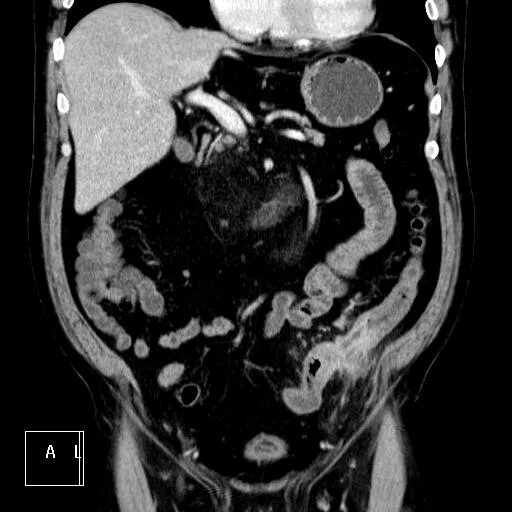

Болит кт